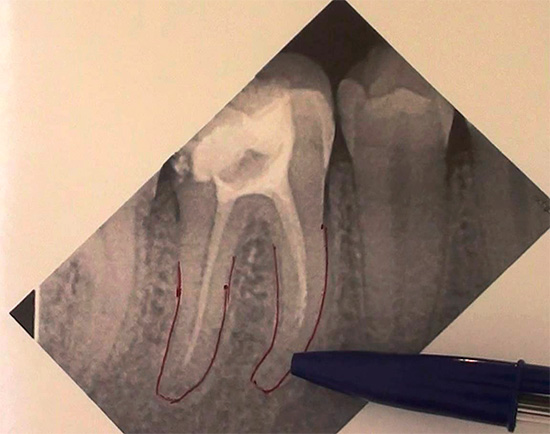

Lascando uma ferramenta em um canal

Se o dentista encontrar pela primeira vez uma complicação como uma quebra do instrumento no canal, na maioria dos casos o médico entrará em pânico (o momento psicológico é acionado - afinal, isso é um erro médico). No entanto, isso, embora não seja o mais frequente, mas, no entanto, um erro de trabalho bastante comum, pode ser corrigido, levando em consideração tecnologias e métodos modernos, e o dente pode ser salvo.

Se durante a limpeza do canal uma parte do instrumento endodôntico se romper nele, se for deixado no canal, o dente começará a doer imediatamente ou após algum tempo. Isso se deve ao fato de que um pedaço do instrumento preso no canal não dá ao médico acesso ao ápice da raiz, devido ao qual permanece uma parte do nervo ou uma infecção não tratada que começará necessariamente a se multiplicar e pode levar a problemas muito grandes no futuro.

A quebra da ferramenta ocorre com mais freqüência devido à falha do médico, e aqui as seguintes razões são possíveis:

- pressão excessiva é aplicada a um instrumento afiado;

- a técnica de uso do instrumento é violada;

- os géis lubrificantes não são utilizados para evitar "congestionamentos" no canal;

- as antigas “agulhas” são usadas repetidamente para limpar e expandir canais (exemplos e arquivos), que passaram pelas etapas de processamento muitas vezes e não são mais adequados.

Mesmo em canais estreitos e fortemente curvados, você pode trabalhar com precisão e corretamente, sem quebrar a ferramenta.

Para evitar possíveis complicações futuras, a remoção imediata dos detritos é realizada usando vários métodos. Por exemplo, o método ultrassônico de "nocautear" um fragmento é atualmente usado ativamente. Outro método de extração é passar um canal ao lado de uma ferramenta presa, expandir, enxaguar, agarrar e removê-lo.

Se for impossível extrair, métodos cirúrgicos conservadores podem ser usados quando a parte passada do canal é selada com cimento e a parte onde o fragmento está localizado é ressecada (a ponta da raiz do dente é cortada).

O método dúbio ainda é o método de impregnação para eliminar a complicação, quando uma poderosa mistura anti-séptica (mais frequentemente resorcinol-formalina) é derramada no canal sobre os detritos do instrumento e um selo é colocado. Geralmente, depois de algum tempo, esses pacientes recorrem novamente ao dentista com uma pergunta - eles dizem que removeram o nervo do dente, mas ainda dói. O método especificado com o uso de pasta de resorcinol-formalina nem sempre resulta, é muito mais confiável remover uma ferramenta quebrada do canal.